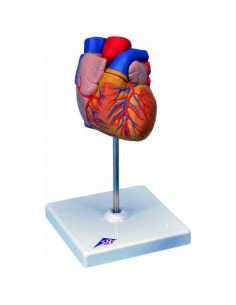

Dal cranio in 22 parti con incastri magnetici ai modelli di colonna vertebrale, da quelli di articolazioni a quelli di cuore, ogni pezzo della nostra collezione è progettato per un’immersione totale nello studio dell’anatomia umana. I nostri modelli, realizzati tramite scansioni di ossa vere, garantiscono un’esperienza tattile autentica e una fedeltà di peso quasi identica agli originali.